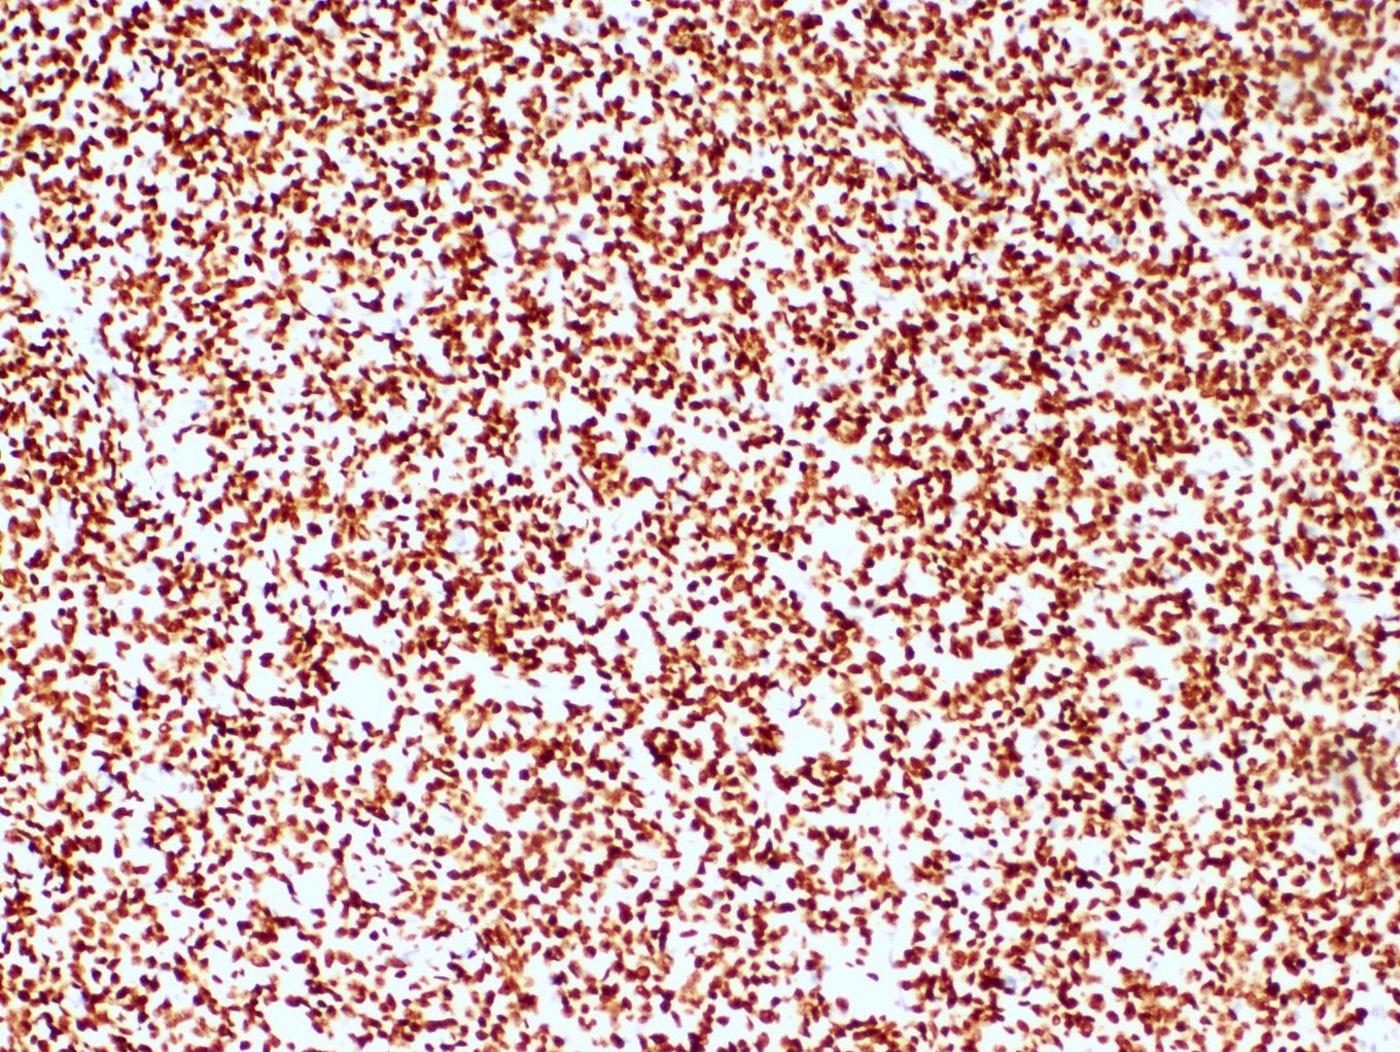

Positive stains

- CD10: sensitivity 91%, specificity 45% (Int J Gynecol Pathol 2018;37:372)

- IFITM1: sensitivity 83%, specificity 70% (Int J Gynecol Pathol 2018;37:372)

- WT1, ER (40 - 100%), PR (69 - 100%)

- Keratins: AE1 / AE3, CAM5.2, MNF 116, CK8 / 18

- Smooth muscle markers (SMA, desmin, caldesmon) often positive in areas of smooth muscle differentiation

- Sex cord markers (inhibin, calretinin, CD99, MelanA, WT1) may be positive in areas of sex cord differentiation

- Beta catenin: nuclear staining without associated mutation (Mod Pathol 2008;21:756)